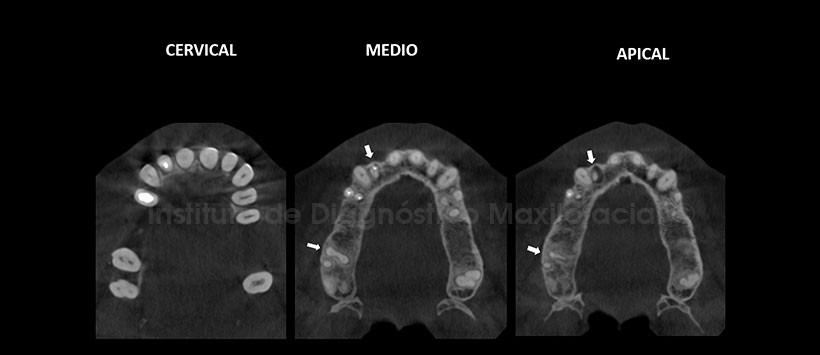

A la evaluación de la tomografía volumétrica (CBCT) mediante cortes axiales y cortes transaxiales (Figura 2 y 3), se visualiza la fusión de la raíz mesio-vestibular con la raíz palatina de la pieza 17 (variante anatómica), además de corroborarse el ensanchamiento periodontal y el defecto óseo angular por mesial. Se aprecia además, en la pieza 21 obturación de conducto en falsa vía y perforación hacia la superficie vestibular del tercio apical radicular asociado a proceso osteolitico pararadicular y periapical.